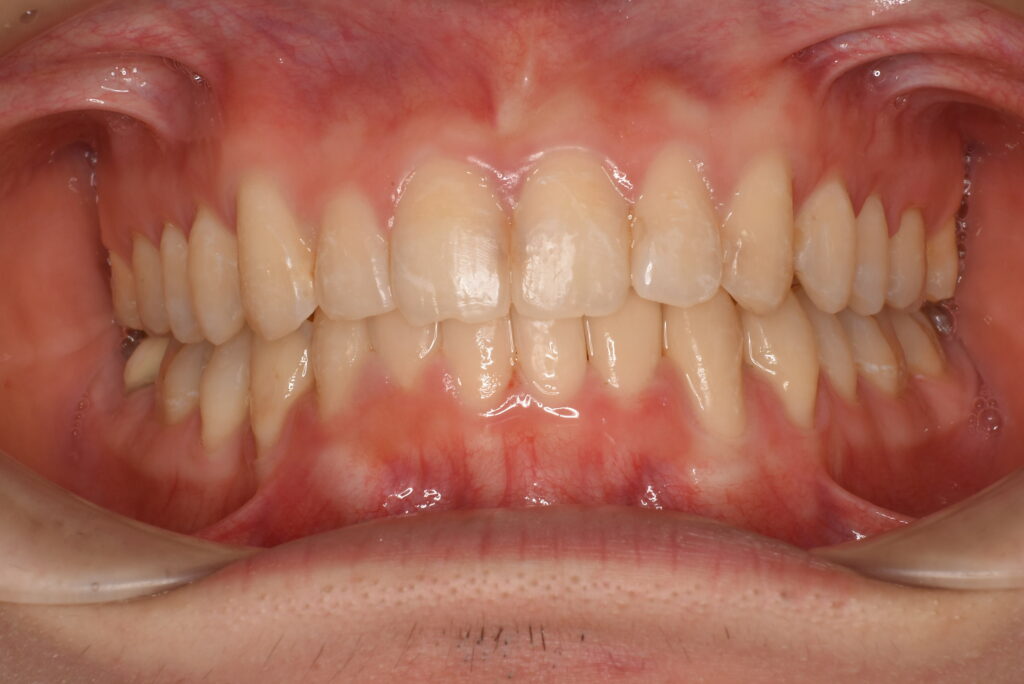

- BEFORE

- AFTER